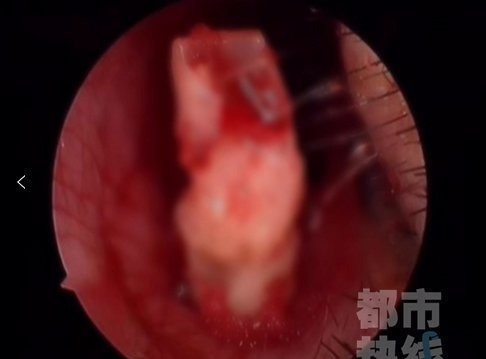

随后,医院为孩子安排了手术!医生剥开女孩鼻腔里牙齿周围的粘膜,在鼻腔狭窄的空间里,将这颗“失联”了三年的牙齿完整拔出,所幸术后孩子恢复良好。

据西安市第三医院耳鼻喉科王延辉主任介绍:临床上鼻腔里“长牙”的情况称为“鼻腔异位牙”,形成的原因有两种:一种是先天性的,多由牙胚萌出受阻产生异位,这种情况少见;一种是后天性的,由于生长发育的原因,儿童牙齿根部和鼻腔底部之间仅相隔一层薄薄的骨质,在外伤等情况下,可能会造成骨质破损,导致牙齿自破损处进入鼻腔,这种情况非常罕见。医生提醒:孩子摔伤掉牙,一定要引起重视,务必找到脱落的牙齿,必要时至医院行相关检查。最近公众号平台更改了推送规则不再按时序展现如果你不和我们互动以后可能就再也收不到我们的推送了所以如果不想错过内容